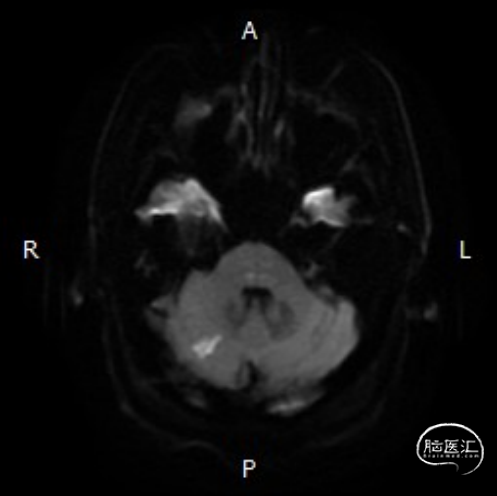

➢头颅MRI:

双侧小脑半球以及桥脑急性缺血性梗死。